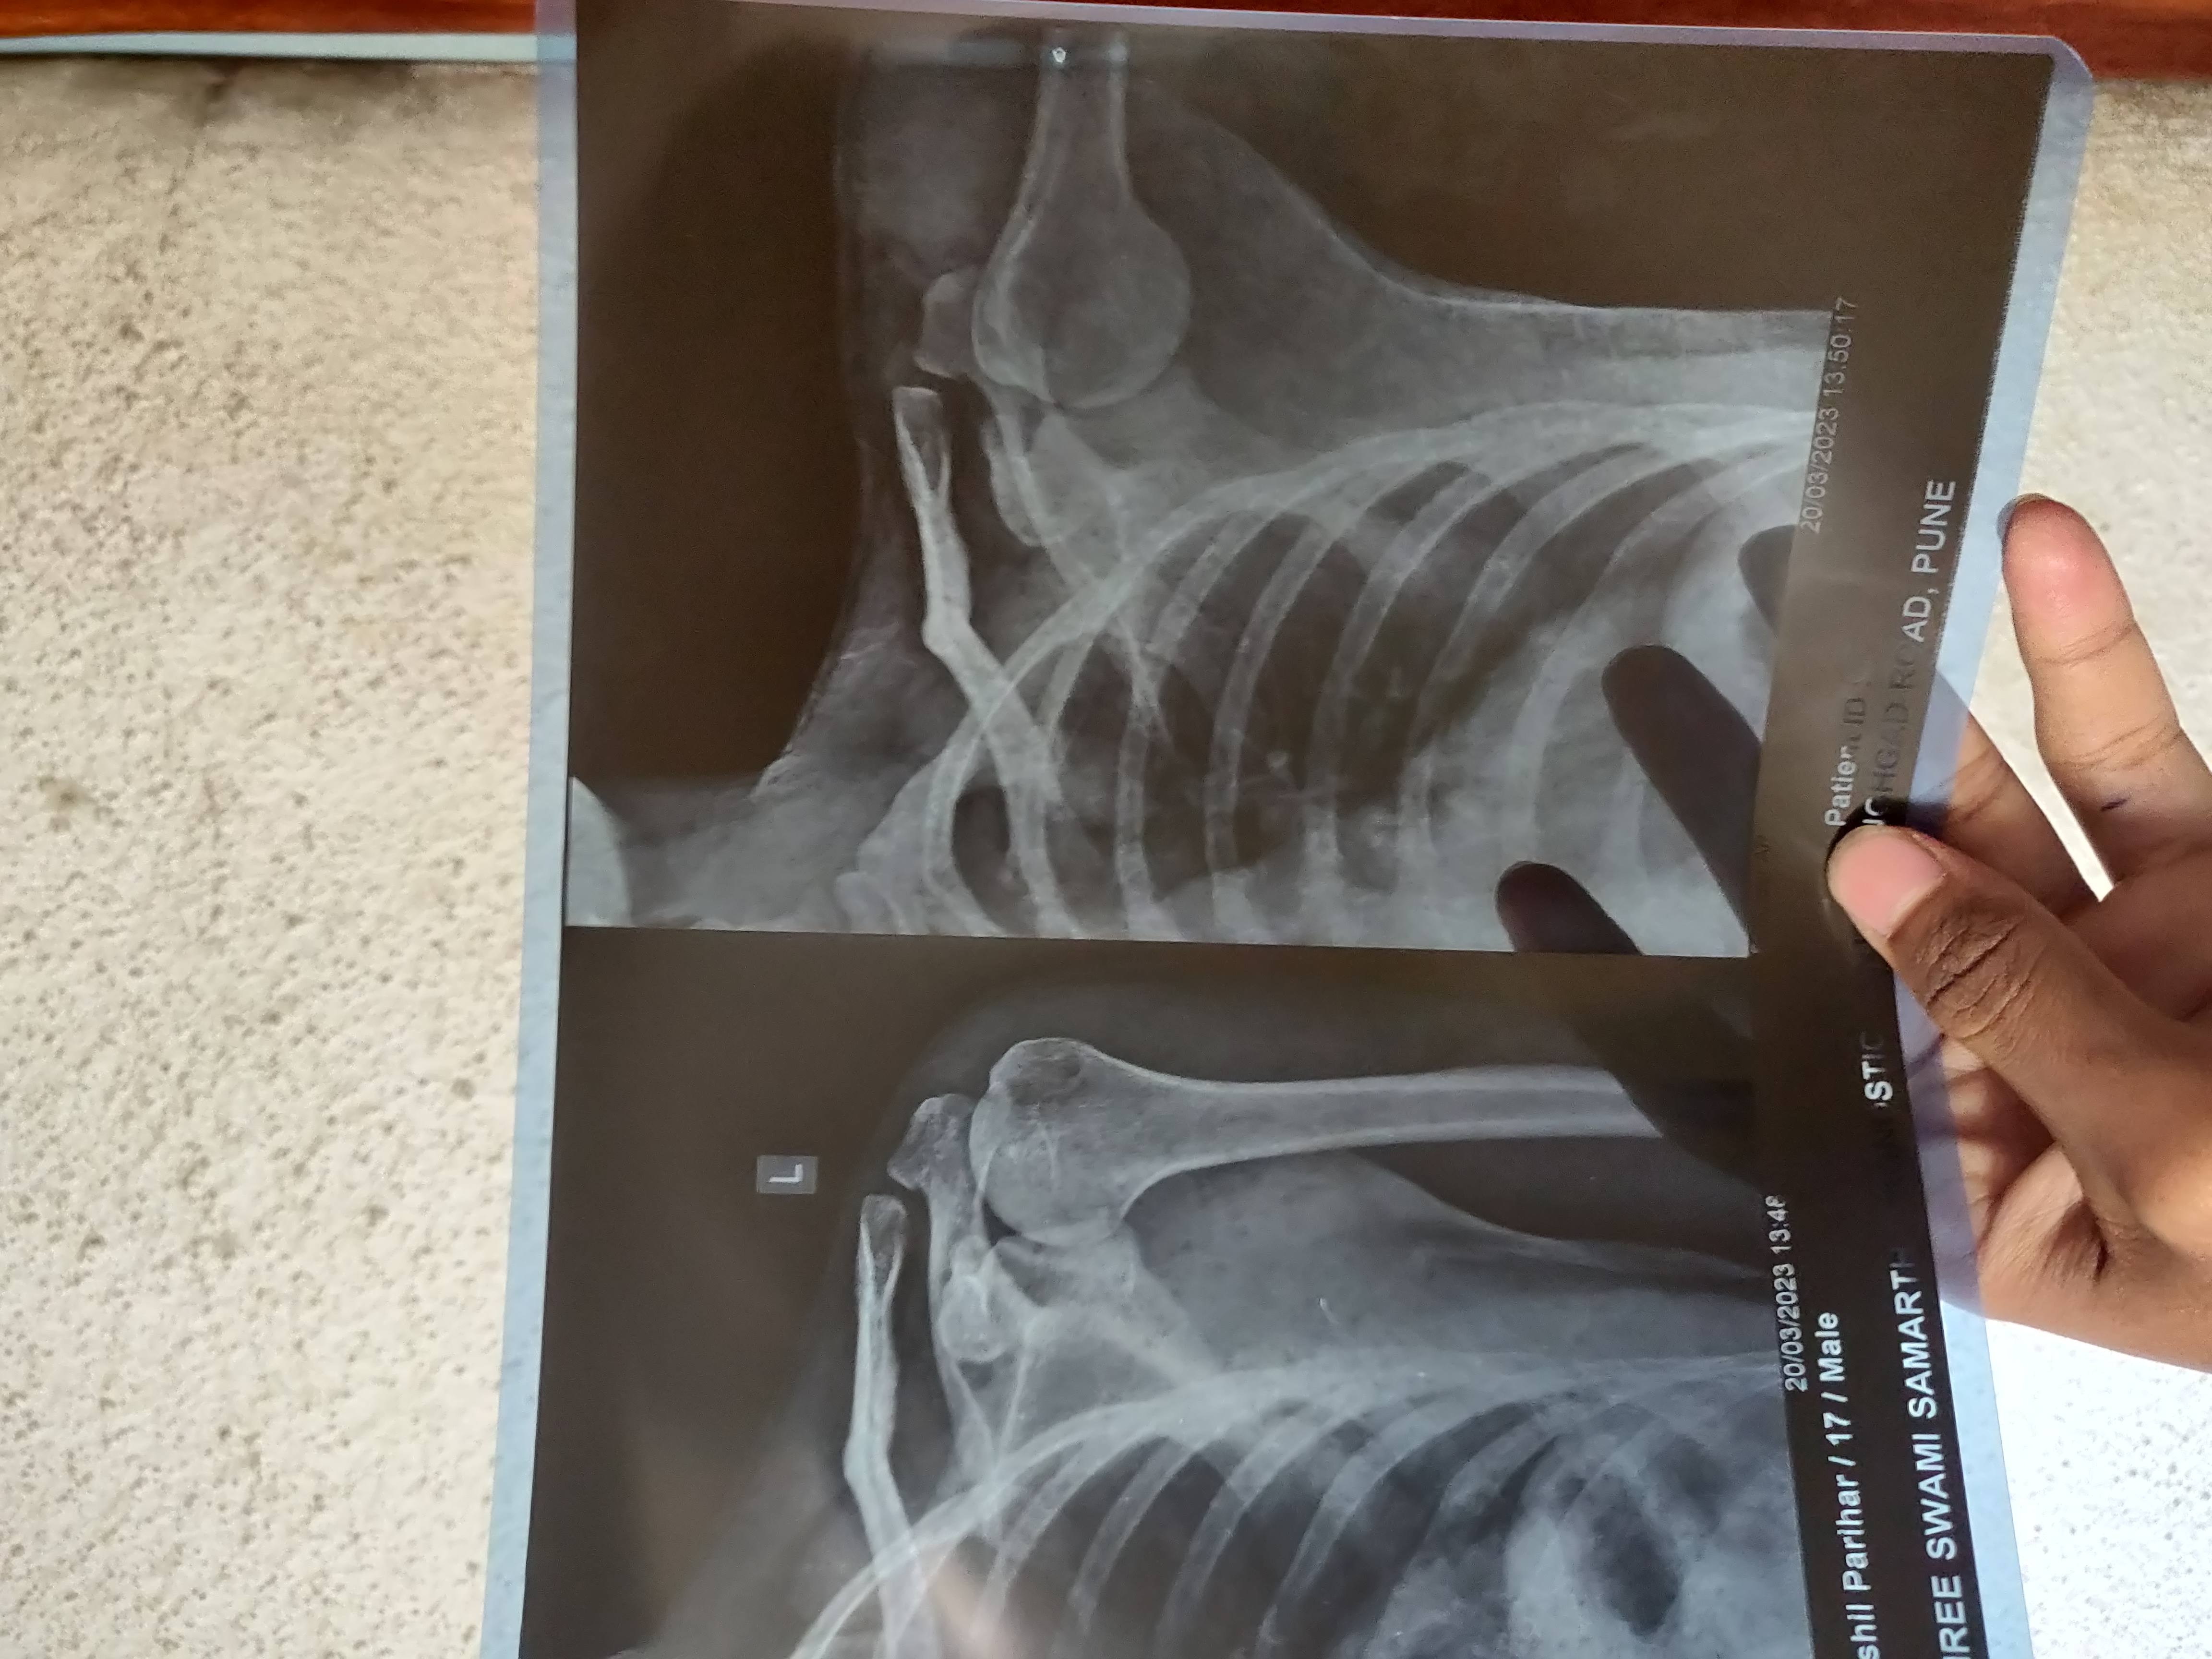

Fractureat the mid shaft of left clavicle.

Bones show normal density and architecture.

The joint space and integrity is well maintained.

Soft tissues appear normal.

Suggest :- Clinical correlation & further evaluation.